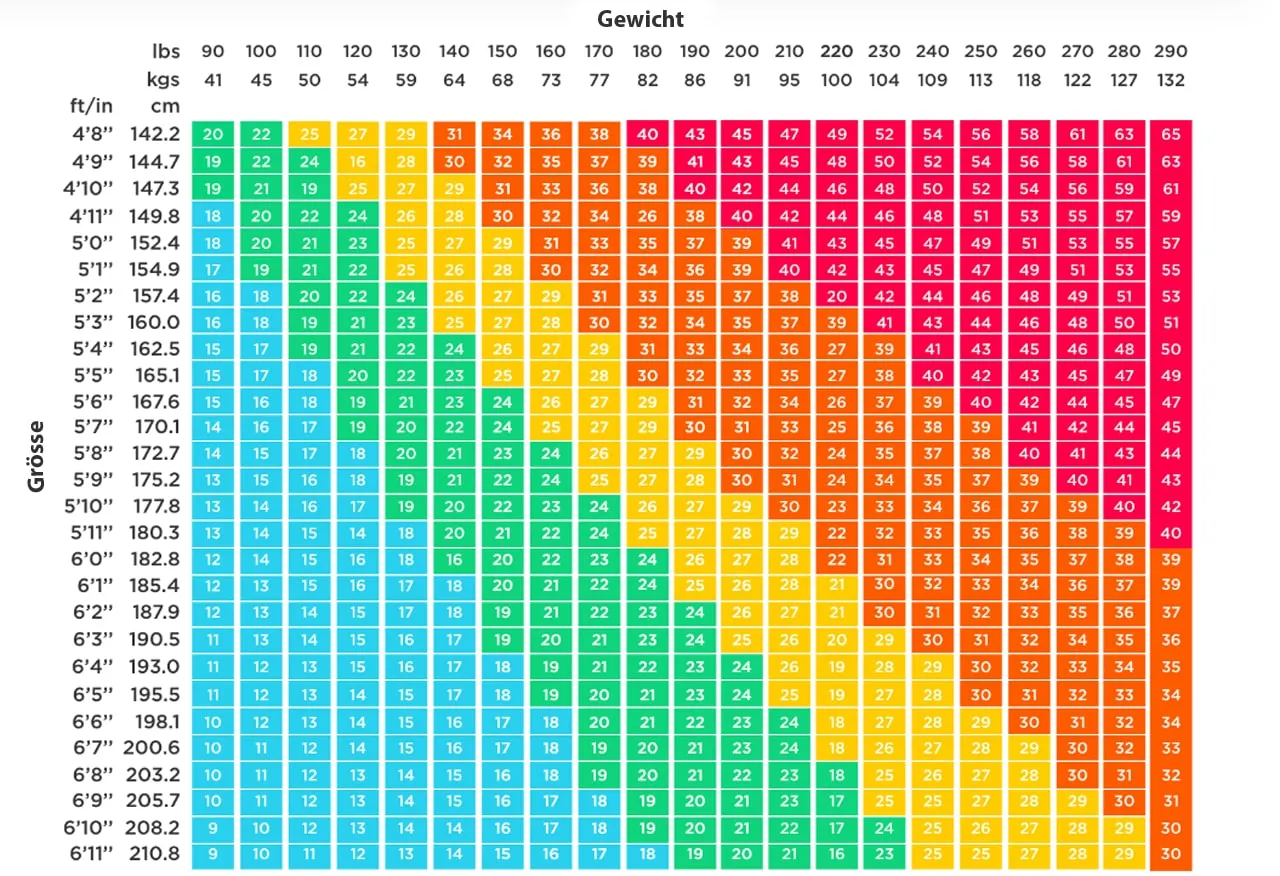

Der Body Mass Index

Zusammen mit der Körpergrösse kann über die Formel Körpergewicht (Kg) /Körpergrösse2 (m2) der so genannte Body Mass Index, der BMI berechnet werden.

Auch dieser Wert unterliegt gewissen Limitationen.

Zwar definiert die WHO über den BMI Übergewicht und Adipositas (Fettleibigkeit), jedoch ist der Wert gerade bei Sportlern schwierig zu bewerten, da der oftmals erhöhte Anteil der Muskelmasse den Wert verfälschen kann.

Body Mass Index Tabelle